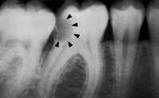

Las radiografías ayudan a estimar la profundidad de

desmineralización por caries en el esmalte y la dentina. La

profundidad no siempre está asociada con la presencia de

cavidad de caries, en especial en superficies proximales.

Investigaciones

clínicas que se realizaron en un país con una tasa baja de

progresión de caries revelaron que, en promedio, el 32% de

las lesiones visibles radiográficamente que se extendían

hasta el tercio externo de la dentina no había cavidad de

caries; por el contario, el 72% de las lesiones que se

extendían hasta 2/3 partes de la dentina tenían cavidad de

caries (33) Las

lesiones con cavidad de caries clínicamente o las lesiones

con obvia radiolucidez en dentina (más profunda que el 1/3

externo) en la superficie oclusal están altamente infectada

la dentina, debajo de la unión amelo-dentinaria (34,35)

Figura 5 |

El ICCMS clasifica radiográficamente las superficies

posteriores de los dientes (36,37) Se

ha reportado que tanto la reproducibilidad como la precisión

de este sistema de clasificación son de significativas (33)

a excelentes (37)

La evidencia

indica que la profundidad de penetración radiográfica en la

que se puede predecir de forma confiable que la superficie

del diente está cavitada y que la dentina está muy

infectada, es cuando la radiolucidez está más alla del

tercio externo de dentina (7,34,35,38,40).

Esto corresponde a los códigos 4, 5 y 6 en el sistema de

clasificación radiográfica de ICCMS. Ver tabla 6. En casos en que las

tasas de progresión son rápidas, se puede esperar que en

lesiones con clasificación 3 en el sistema descrito

anteriormente, haya formación de cavidad.